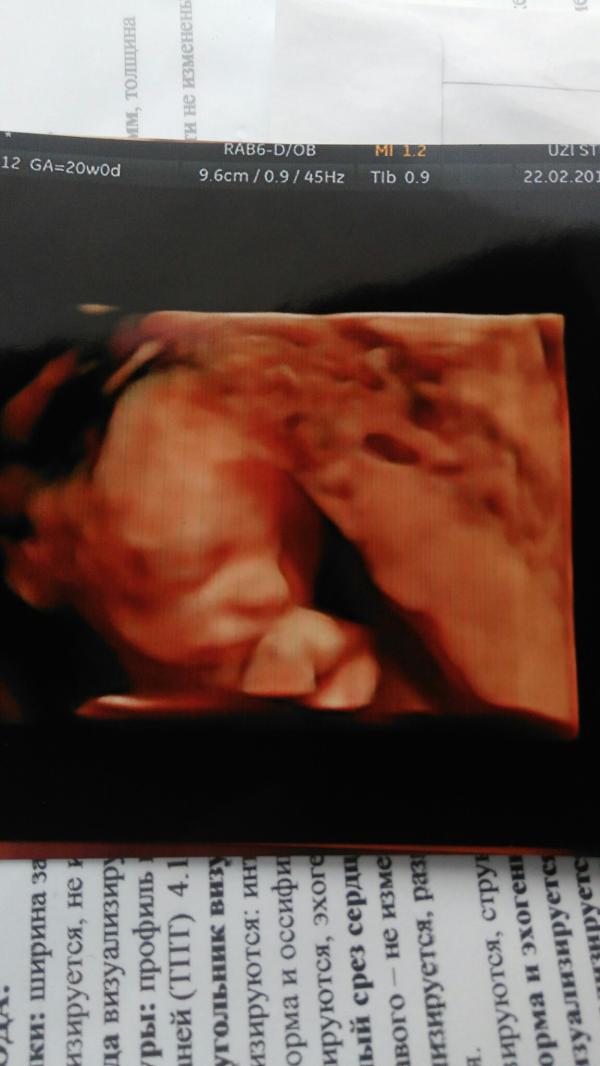

Вот и наступил у нас экватор😆 сегодня переделала скрининг в УЗИ студии. Предыстория. Неделю назад делала в горбольнице, написали мне в заключении 2 степень зрелости плаценты, тенденцию к маловодию и низкую плацентацию. Я побежала к врачу она назначила Курантил и сказала приходить когда назначен прием. Я решила переделать скрининг и это было правильное решение. Маловодие исключили, степень зрелости 0. Низкая плацентация подтвердилась, но она и была. На первом скрининге перекрывала на 1,5 см. На втором в горбольнице поднялась, была 1,7 от края. Сегодня 2,6 от края. Так что поднимается родненькая.

Нам подтвердили девочку и я сама видела что это 💯 девочка. Ураааааааааа

В УЗИ студии, 5 фотографии и диск ещё фото и видео